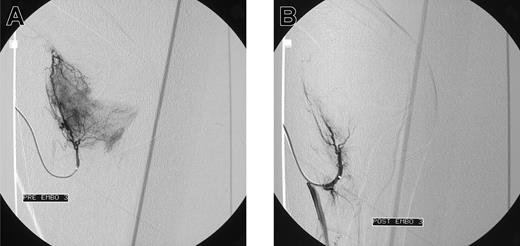

Initial angiograms demonstrated a blush, indicative for hyperemic tissue as cause of bleeding in 15 patients (Figure 1A-B); in 2 patients a false aneurysm was observed (Figure 2A-B); in one patient a true aneurysm was observed; and in 3 patients an arteriovenous shunt in combination with an aneurysm was observed. In all these cases embolization of the feeding arteries was performed. However, in some cases, it was not possible to embolize all the bleeding arteries. In 2 patients, the cause of bleeding could not be localized (one patients with postoperative knee bleeding and one with spontaneous elbow bleeding) and embolization was not performed.

Blush in a patient with elbow bleeding. Angiogram shows massive blush in a patient with recurrent spontaneous elbow bleeding before (A) and after (B) embolization.

Blush in a patient with knee bleeding. Angiogram shows blush in a patient with recurrent massive knee bleeding following joint replacement before (A) and after (B) embolization.